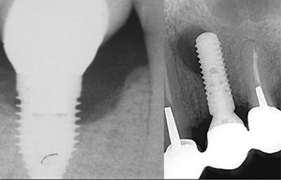

Among the factors associated with the appearance of this pathology are: contamination of the implant surface or surgical bed,11,12 overheating of bone during implant bed preparation,11,13 preparation of an implant bed that is longer than the implant itself,8 pre-existing bone disease,1 presence of residual root fragments or foreign bodies,8,11 premature loading causing bony microfractures,14 and implant placement in proximity to an infected maxillary sinus.14 Some studies have suggested the most likely cause is endodontic pathology of the tooth replaced by the implant or adjacent tooth.9,10 Figure 2 shows an intraosseous tract within the mandible from a periapical lesion of a tooth leading to RPI of the adjacent implant.

Fig 2. Panoramic radiograph (left) and CBCT (right) showing intraosseous tract from a periapical lesion of a tooth leading to RPI of the adjacent implant.

Figure 2